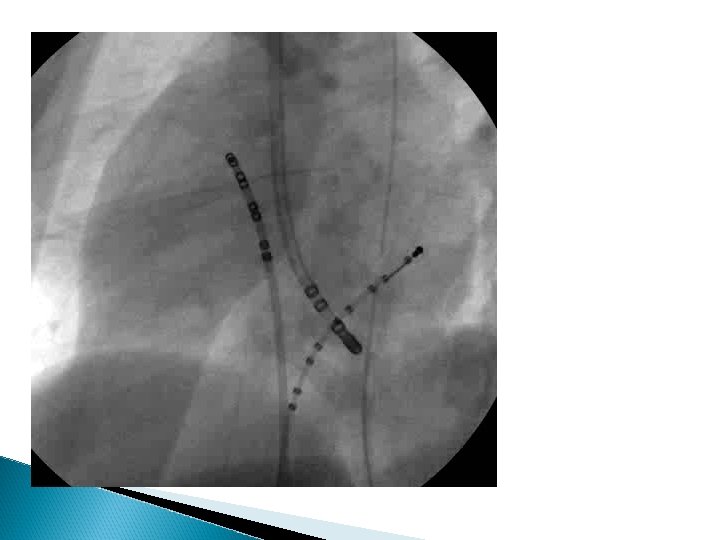

Koroner Sinüsten Kriyoablasyon Collins K ve ark. J Cardiovasc Electrophysiol 2007